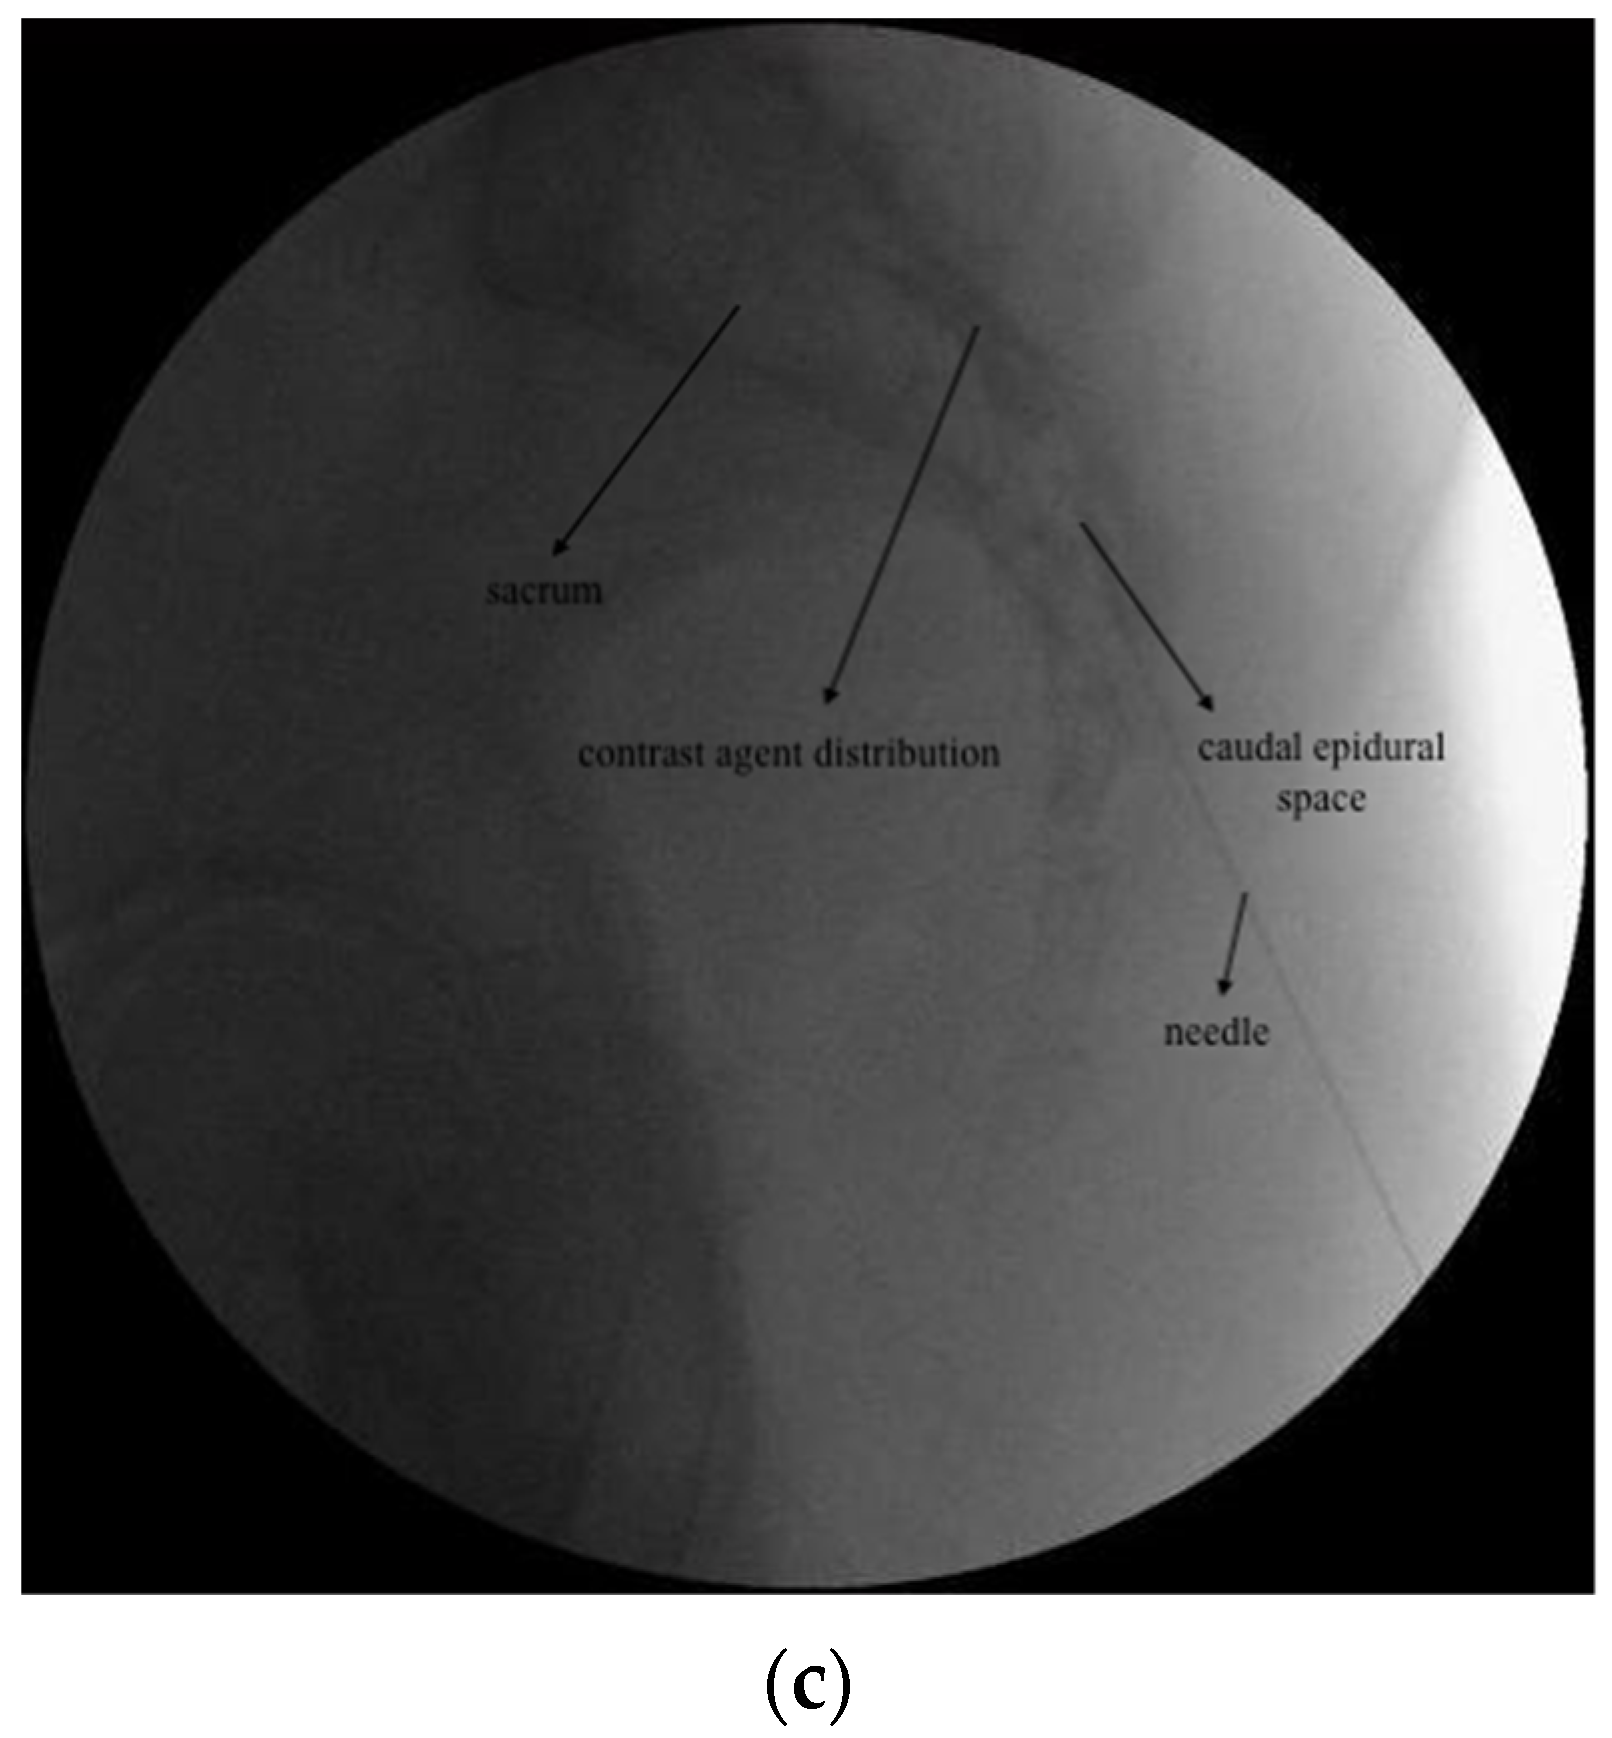

2.3.2. CESI